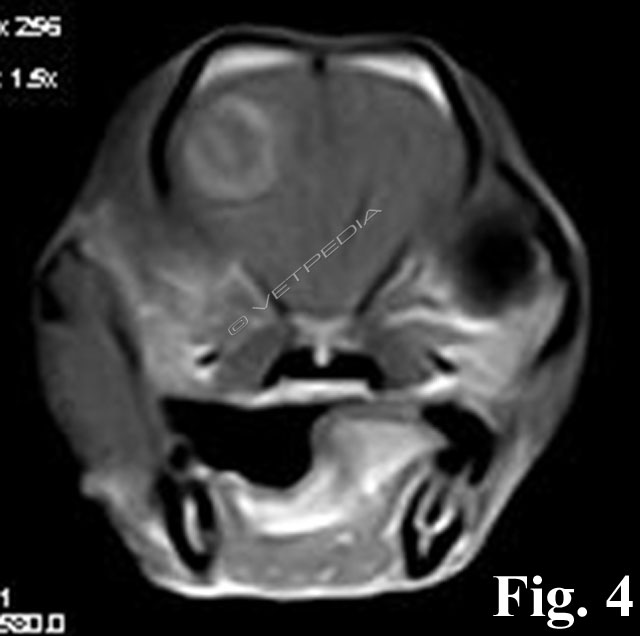

La misurazione dell’ormone adrenocorticotropo (ACTH) endogeno rappresenta un test di laboratorio utile per valutare la funzionalità dell’asse ipotalamo-ipofisi-surrene (HPA) (Fig. 1) qualora si sospetti una patologia endocrina di origine ipofisaria o surrenalica. L’ACTH è un ormone estremamente labile e sensibile alle alte temperature e p...